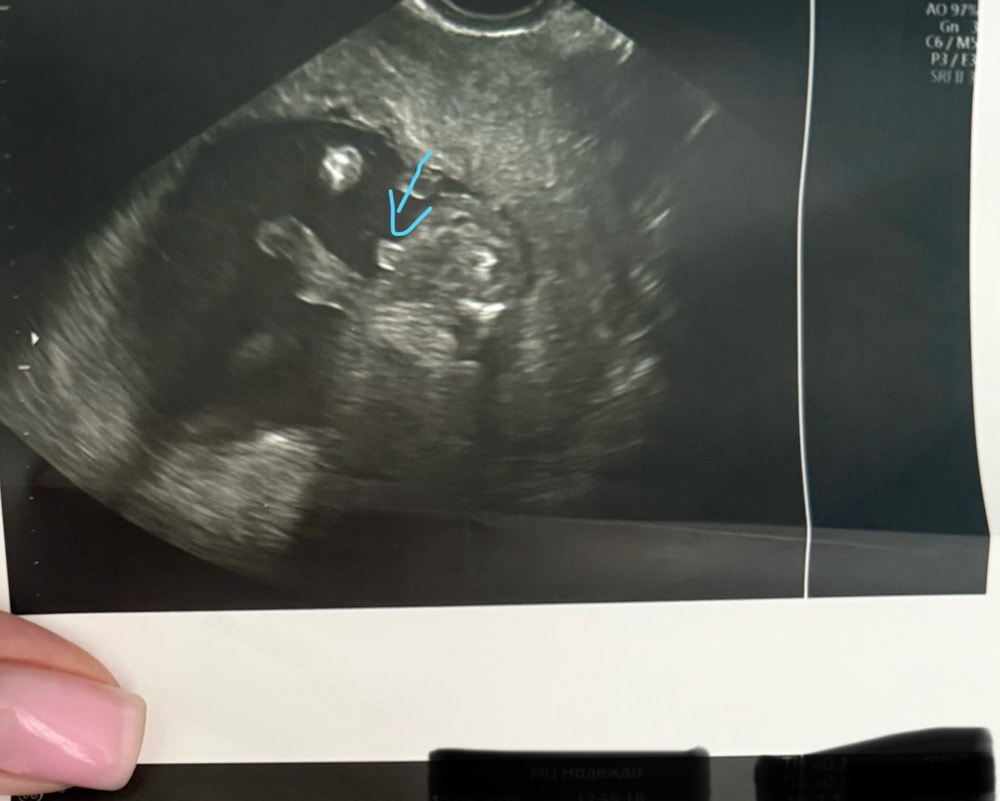

Мальчик в 16 недель Ракурс снизу вверх между ножек Изображение